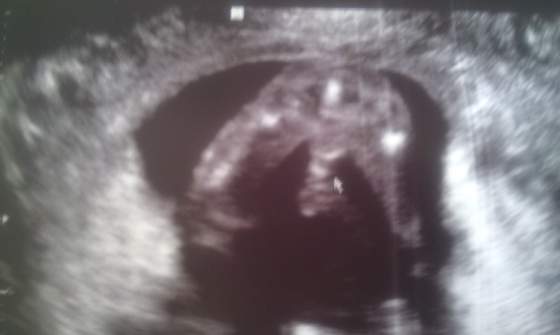

zaraz będą połówkowe to każda będzie już pewna maleństwa, mój Synio strasznie spokojny dzisiaj ani razu nie dotknął mnie, smutno ...